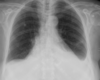

Diagnose?

Pneumothorax

- Der Lungenrand ist sichtbar.

- Der Pneu ist eine strukturlose Aufhellung.